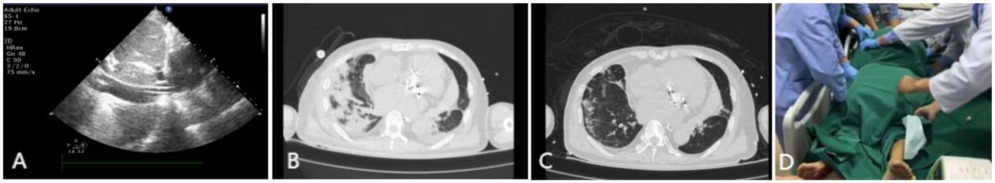

Upon arrival at the intensive care unit (ICU), the patient's oxygen saturation fluctuated between 70% and 90% despite escalation to 100% of inspired oxygen. Arterial blood gas analysis revealed a PaO2 of 59 mmHg. The patient experienced a continuous decline in the oxygenation index (PaO2/FiO2) to <100 mmHg. Large volume of serous secretions were aspirated through the endotracheal tube. The CXR (Figure 1A) revealed partial atelectasis of the left lung and diffuse infiltrates in the right lung, which confirmed the presence of RPE in the right lung. A lung-protective ventilation strategy was immediately instituted, with a target tidal volume of 6 ml/kg, a driving pressure of 16 cmH2O, and a positive end-expiratory pressure (PEEP) of 12 cmH2O. Subsequently, a lung-protective ventilation strategy — with a target tidal volume of 6 ml/kg, driving pressure of 16 cmH2O, and positive end-expiratory pressure (PEEP) of 12 cmH2O — was implemented, along with sedation, muscle relaxation, and diuretic therapy for pulmonary edema. However, the patient's oxygenation failed to improve, and severe respiratory acidosis developed in conjunction with extremely unstable vital signs. The primary postoperative manifestation was refractory hypoxemia. Transthoracic echocardiography was limited by pulmonary edema and air artifacts, precluding a full assessment. However, the limited views available indicated that cardiac function was satisfactory. Following a rapid discussion among a multidisciplinary team comprising cardiothoracic surgery, intensive care, and the ECMO team, the decision was made to initiate VV-ECMO support. A 19Fr cannula was percutaneously inserted into the right internal jugular vein. Additionally, a 23Fr venous cannula was introduced through the common femoral vein to the inferior vena cava and positioned at the right atrium orifice (Figure 3A). VV-ECMO circuit was established via the right internal jugular and right femoral veins at a flow rate of 4.0 L/min with 100% oxygen. Following ECMO initiation, the patient's oxygenation improved rapidly, allowing for a significant reduction in mechanical ventilation parameters to achieve a “lung rest” strategy (FiO2 < 40%, tidal volume 4–6 ml/kg, PEEP 10–12 cmH₂O).

During his ICU stay, serial assessments—including CXR (Figures 1A–D), lung ultrasounds (Figures 2A–D), computed tomography (CT; Figures 3B,C), and blood gas analyses—were obtained to monitor his condition. The chest CT revealed significant exudation in the right dorsal segment. Based on this finding, prone positioning ventilation (PPV) was initiated as an adjunct to the ongoing VV-ECMO therapy to treat the RPE (Figure 3D). By postoperative day 10, the patient's CXR demonstrated marked improvement and lung auscultation findings were unremarkable, enabling the discontinuation of VV-ECMO. The patient was successfully extubated on postoperative day 12 and was subsequently discharged on postoperative day 30 without sequelae. Transthoracic echocardiography prior to discharge demonstrated normal function of the prosthetic valve. Informed consent was obtained from the patient for the publication of his clinical details and images.

Figure 3. Imaging findings during VV-ECMO therapy. (A) Ultrasound confirming the positioning of the vena cava catheter tip at the orifice of the right atrium. (B) Thoracic CT on postoperative day 6 demonstrating pulmonary edema in the right lung. (C) Follow-up CT on postoperative day 13 showing significant improvement in right lung exudation. (D) Illustration of VV-ECMO therapy combined with PPV.